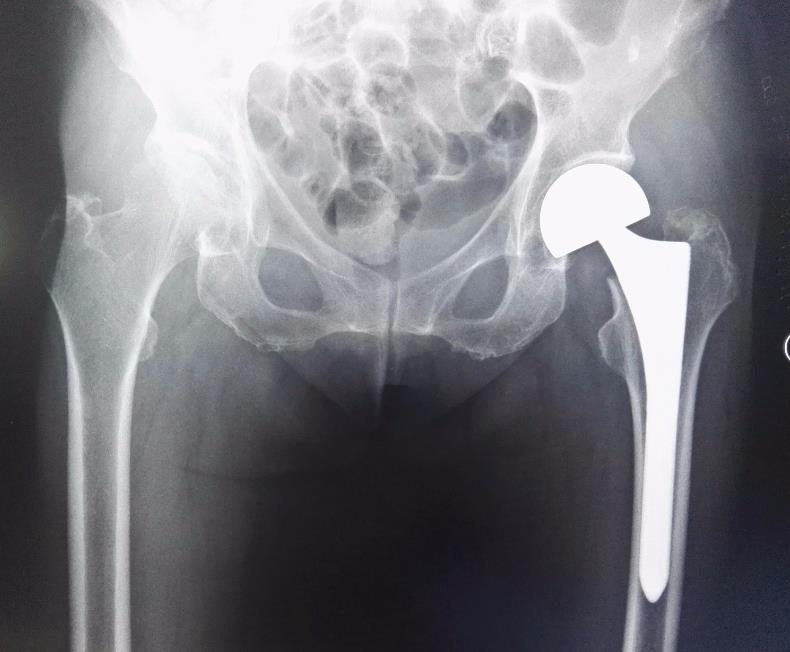

第四名:股骨骨折

被排名第四位的是股骨骨折。

提到骨折,任何一根骨头骨折都让人难以招架,更何况是你体内最粗壮、最坚固的骨头——股骨骨折。

人的股骨是下肢主要负重骨之一。

再加上沿着腿部延伸的所有大动脉,如果不幸股骨骨折,这骨折会占人体全身骨折的4%-6%,那真的要痛不欲生。

股骨骨折一般是因为,某种严重事故(例如运动损伤或车祸)引起的,当该区域骨折时,碰到一点儿都会立即让人们尖叫。

就不用说在受伤的腿上,施加任何重量,更不用说是在行走了。

老年人也是股骨骨折的高发人群。

这主要是由于老年人的骨矿物质密度降低,从而导致骨折易感性增加。并且髋周肌群退化,反应能力下降,无法减轻或抵消外来压力而造成的。

大家都知道,骨折那恢复起来是很慢的。

俗话说,伤筋动骨100天。更何况是股骨骨折,它的恢复过程也是相当艰难的。

首先得将骨头放回正确的位置,医生会通过手术放置一些“硬件”支撑。

然后,当身体再生新的骨头生长出来和原来的骨头,发生冲突产生炎症时,还须要用物理治疗,来加强骨的强度以及骨头周围的肌肉。

想一想就浑身发抖,难以想象股骨骨折,得给人们的生活带来多少不便和疼痛。